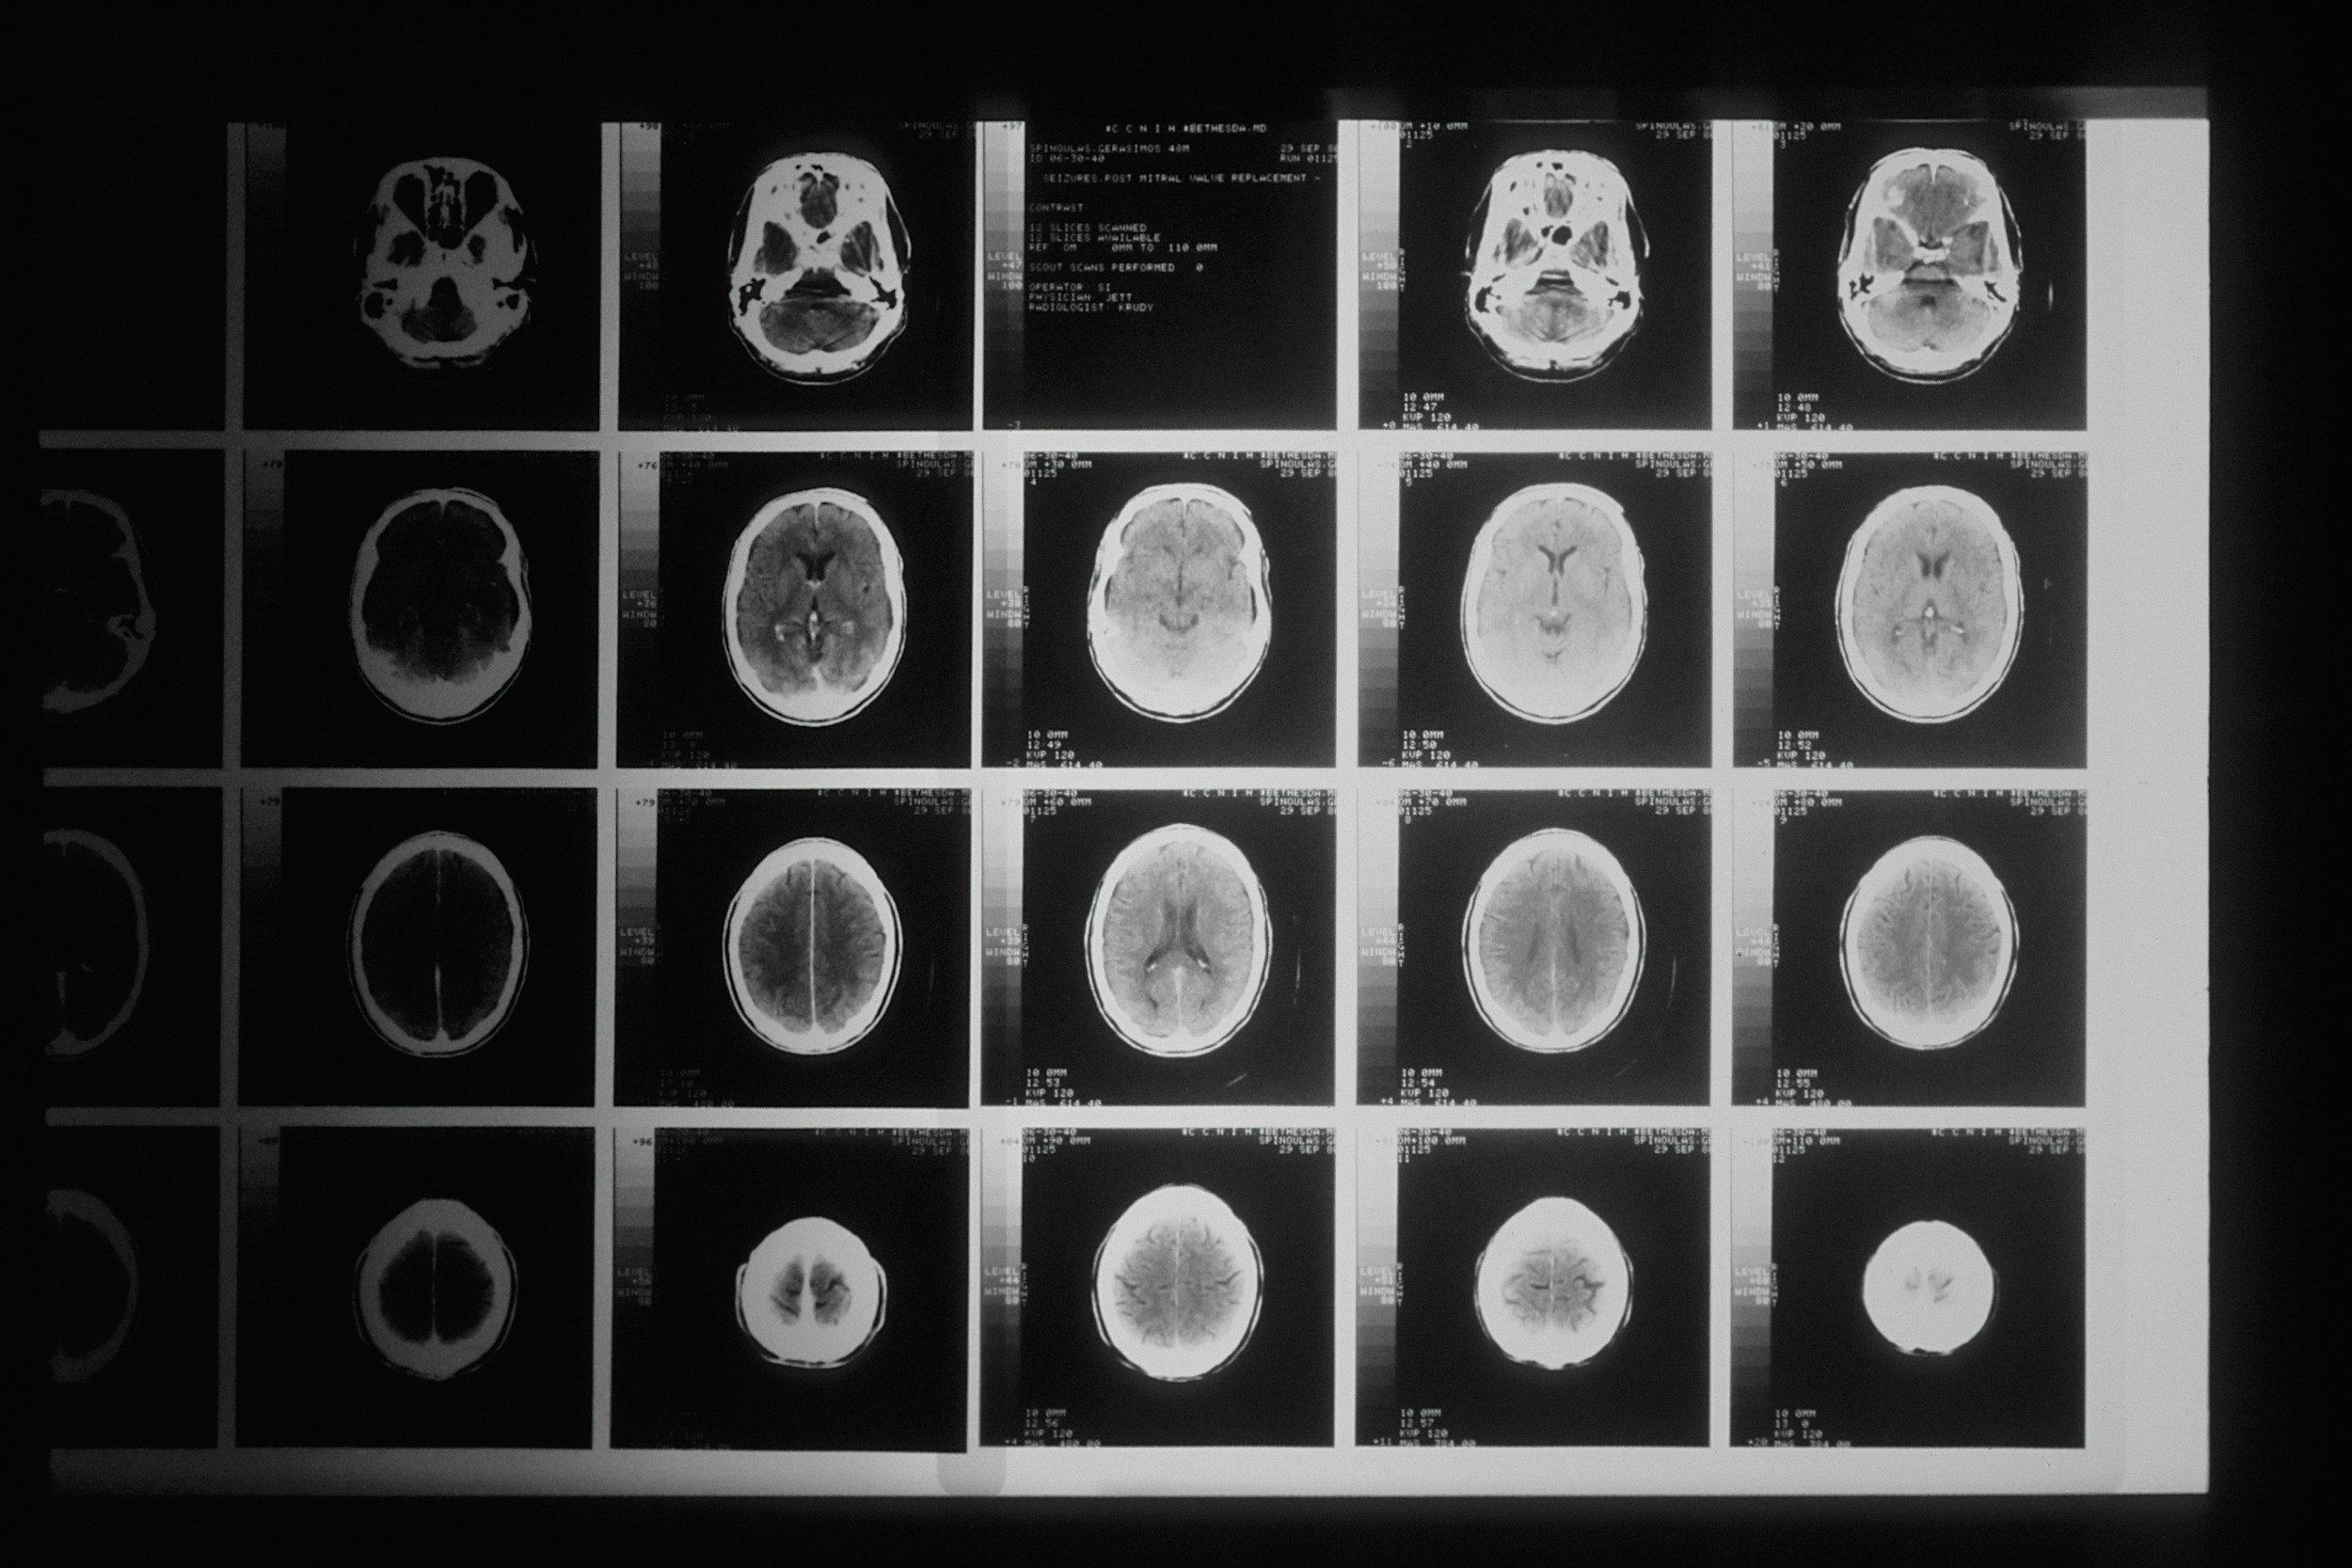

Black and white CT scans of a human brain displayed on a lightbox.